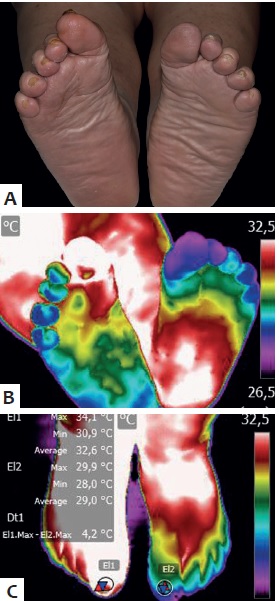

O grande segredo? A neuropatia diabética desliga seu alarme interno de calor.

Seus pés podem estar queimando sem você sentir nada. A verdade é a seguinte: isso transforma um banho relaxante em um risco sério de úlcera.

Aqui está o detalhe: A Sociedade Brasileira de Diabetes é clara: inspeção visual diária é obrigatória.

Uma pequena bolha hoje, ignorada, vira uma ferida profunda em uma semana. O custo? Tratamentos que podem passar de R$ 5.000 e meses de recuperação.

- Passo 3: Use o termômetro de banho, sem erro! – Este é o detalhe que faz toda a diferença! Pegue seu termômetro de banho e mergulhe-o na água. A temperatura ideal para os pés diabéticos deve ser morna, bem próxima à temperatura do seu corpo, entre 32°C e 37°C. A neuropatia diabética compromete a sensibilidade térmica, e um termômetro é a sua garantia de segurança. É a ferramenta mais recomendada por especialistas para evitar queimaduras, que podem virar um problemão sério.

A temperatura ideal para a água dos seus pés deve ser morna, sabe? Algo entre 32°C e 37°C, bem próxima da temperatura do corpo. É o que os especialistas recomendam. Água muito quente pode causar queimaduras sem que você perceba, e água muito fria pode comprometer a circulação. Equilíbrio é a chave aqui para o cuidado dos pés.

Neuropatia Diabética e Sensibilidade Térmica: Como Testar a Água

A neuropatia diabética é traiçoeira, ela diminui a sua capacidade de sentir calor, frio ou até mesmo dor. Por isso, testar a água com o cotovelo ou o dorso da mão é uma alternativa mais segura do que usar os pés. Essas áreas geralmente mantêm a sensibilidade intacta. Mas, de novo, o termômetro de banho é o seu melhor amigo nesse processo, garantindo precisão total.